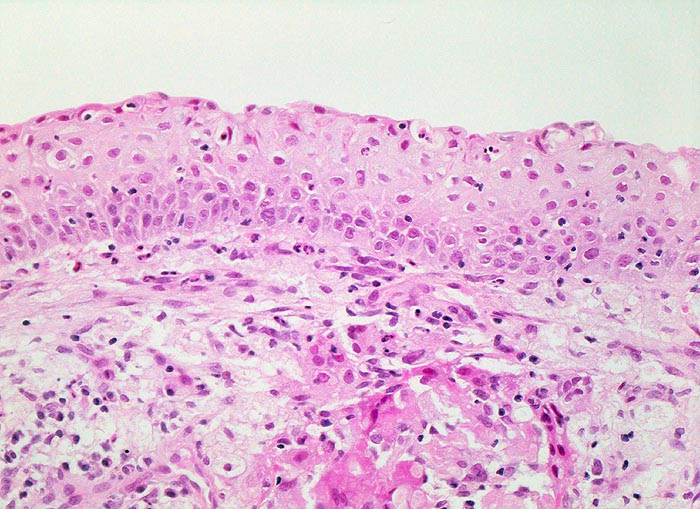

Plattenepithelmetaplasie der Bronchialschleimhaut

Nicht verhornende plattenepithelial differenzierte Schleimhaut. Zytoplasmareiche Epithelzellen ohne Atypien mit scharfen Zellgrenzen. An der Oberfläche fehlen Flimmerhaare. Basalzellschicht mit etwas weniger Zytoplasma. Lockeres granulozytäres Entzündungsinfiltrat im Epithel und im subepithelialen Stroma.

Die Plattenepithelmetaplasie ist Ausdruck einer Anpasssung auf chronische mechanische (z.B. Reibe- und Druckpunkte von Trachealkanülen) bzw. chemische (Zigarettenrauch) Irritation. Häufig findet sich eine Plattenepithelmetaplasien ev. mit Dysplasie in der Umgebung eines invasiven Karzinoms.